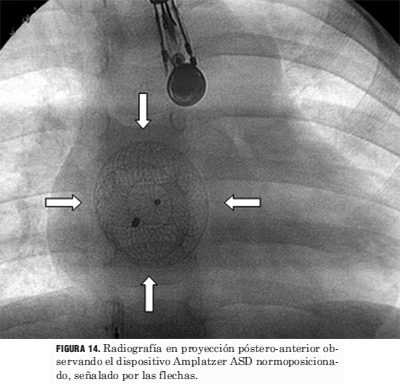

Por último, debemos recordar que con el uso de esta tecnología se han agregado nuevos elementos a valorar en la lectura de la radiografía de tórax (figuras 14 y 15).

Figura 14. Radiografía en proyección póstero-anterior observando el dispositivo Amplatzer ASD normoposicionado, señalado por las flechas.